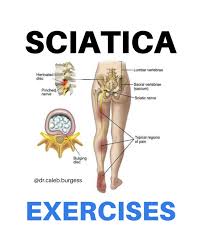

Download Sciatic nerve pain pictures